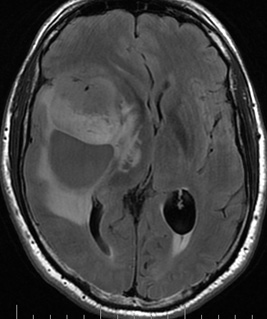

Patient de 57 ans, présentant depuis septembre 2010 des hallucinations olfactives, associées à des épisodes de nausée de durée brève de nature épileptique.

L’examen clinique initial était sans particularité. L’IRM cérébrale objectiva un processus expansif intra-axial fronto-temporal droit kystique, nécrotique et charnu prenant le contraste. Une biopsie stéréotaxique a été réalisée et est en faveur d’un glioblastome de haut grade selon la classification OMS.

Le traitement consiste en une radiothérapie avec chimiothérapie par